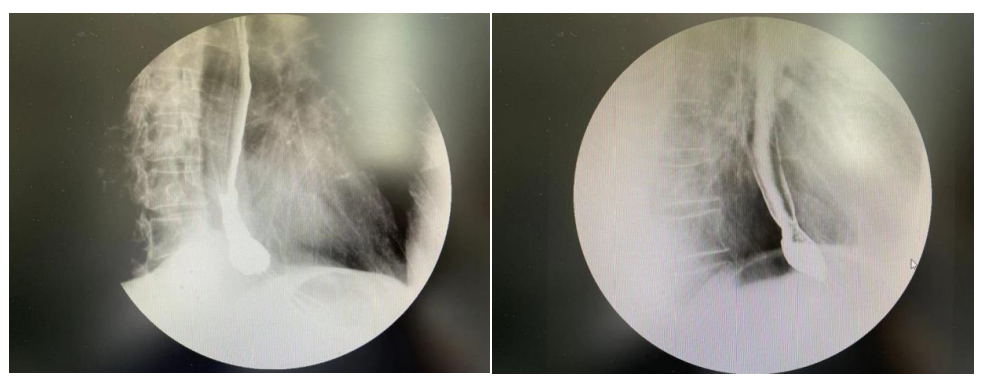

放疗前,放疗后食管钡餐造影对比图像

因患者有严重的慢性肺阻塞性疾病,计划优化过程中尽量降低双肺低剂量受照体积。放疗期间予以奥沙利铂+替吉奥双药同步放化疗。治疗期间出现II度骨髓抑制,I度消化道反应,治疗过程中吞咽困难逐步改善,放疗结束后进食梗阻症状完全消失。